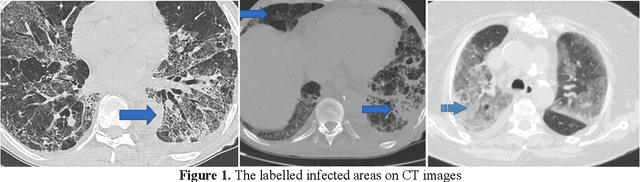

Abstract:Coronavirus (COVID-19) emerged towards the end of 2019. World Health Organization (WHO) was identified it as a global epidemic. Consensus occurred in the opinion that using Computerized Tomography (CT) techniques for early diagnosis of pandemic disease gives both fast and accurate results. It was stated by expert radiologists that COVID-19 displays different behaviours in CT images. In this study, a novel method was proposed as fusing and ranking deep features to detect COVID-19 in early phase. 16x16 (Subset-1) and 32x32 (Subset-2) patches were obtained from 150 CT images to generate sub-datasets. Within the scope of the proposed method, 3000 patch images have been labelled as CoVID-19 and No finding for using in training and testing phase. Feature fusion and ranking method have been applied in order to increase the performance of the proposed method. Then, the processed data was classified with a Support Vector Machine (SVM). According to other pre-trained Convolutional Neural Network (CNN) models used in transfer learning, the proposed method shows high performance on Subset-2 with 98.27% accuracy, 98.93% sensitivity, 97.60% specificity, 97.63% precision, 98.28% F1-score and 96.54% Matthews Correlation Coefficient (MCC) metrics.

Abstract:This study presents early phase detection of Coronavirus (COVID-19), which is named by World Health Organization (WHO), by machine learning methods. The detection process was implemented on abdominal Computed Tomography (CT) images. The expert radiologists detected from CT images that COVID-19 shows different behaviours from other viral pneumonia. Therefore, the clinical experts specify that COV\.ID-19 virus needs to be diagnosed in early phase. For detection of the COVID-19, four different datasets were formed by taking patches sized as 16x16, 32x32, 48x48, 64x64 from 150 CT images. The feature extraction process was applied to patches to increase the classification performance. Grey Level Co-occurrence Matrix (GLCM), Local Directional Pattern (LDP), Grey Level Run Length Matrix (GLRLM), Grey-Level Size Zone Matrix (GLSZM), and Discrete Wavelet Transform (DWT) algorithms were used as feature extraction methods. Support Vector Machines (SVM) classified the extracted features. 2-fold, 5-fold and 10-fold cross-validations were implemented during the classification process. Sensitivity, specificity, accuracy, precision, and F-score metrics were used to evaluate the classification performance. The best classification accuracy was obtained as 99.68% with 10-fold cross-validation and GLSZM feature extraction method.